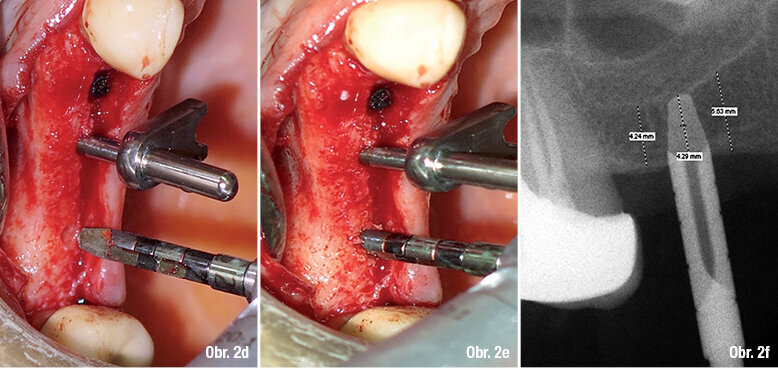

Obr. 2d: 2,5 mm rotační fréza bez řezacích hran pro započetí rozšiřování osteotomie na krestální kosti Obr. 2e: Perforace 2,5 mm rotační frézou pro rozšiřování kosti Obr. 2f: RTG snímek znázorňující reziduální výšku alveolární kosti (4,24 mm) a také vložení 2,5 mm rotační frézy do kosti (4,29 mm).

Řez byl veden intrasulkulárně pomocí čepelky č. 15 uchycené v Bard-Parker skalpelu. V dané oblasti byl odklopen mukoperiostální lalok a poté byl dodržen výše zmíněný protokol pro ISL: Preparace pilotním vrtákem (průměr 2 mm) pro dosažení kortikální perforace. Délka preparace (1–2 mm) byla stanovena na základě reziduální výšky alveolární kosti před měřením (obr. 1b). Používá se vysokorychlostní vrtačka (1100 rpm) s externím vodním chlazením a aktivními řezacími hranami v apikální části. Osteotomie pomocí pilotu by měla být o 1–2 mm kratší než RBH změřená na periapikálním RTG snímku. Následující kroky byly provedeny pomocí rotačních fréz (50 rpm) bez chlazení vodou. Tyto frézy sestávají ze dvou vertikálních řezacích hran, které končí 2 mm před apikální částí. Apex je zúžený a bez řezací hrany, aby nezpůsobil perforaci Schneiderovy membrány. Pro počáteční rozšiřování krestální kortikální kosti byla použita 2,5 mm ruční fréza. Tlakem prstu bylo docíleno prohloubení skrze kortikální kost čelistní dutiny. Tlak umožní neaktivní hraně frézy protlačit se skrze spongiózu, ale zastavit se o tvrdé tkáně dna čelistní dutiny (obr. 2d). S touto 2,5 mm frézou byl zhotoven RTG snímek, abychom stanovili finální délku pod dnem čelistní dutiny (obr. 2f). Byla změřena reziduální výška alveolárního hřebene (RBH) pro ozřejmění definitivní délky preparace a zavedeny frézy pro zvětšení průměru otvoru o 0,5 mm, dokud se nedosáhlo 4,5 mm průměru implantátu.